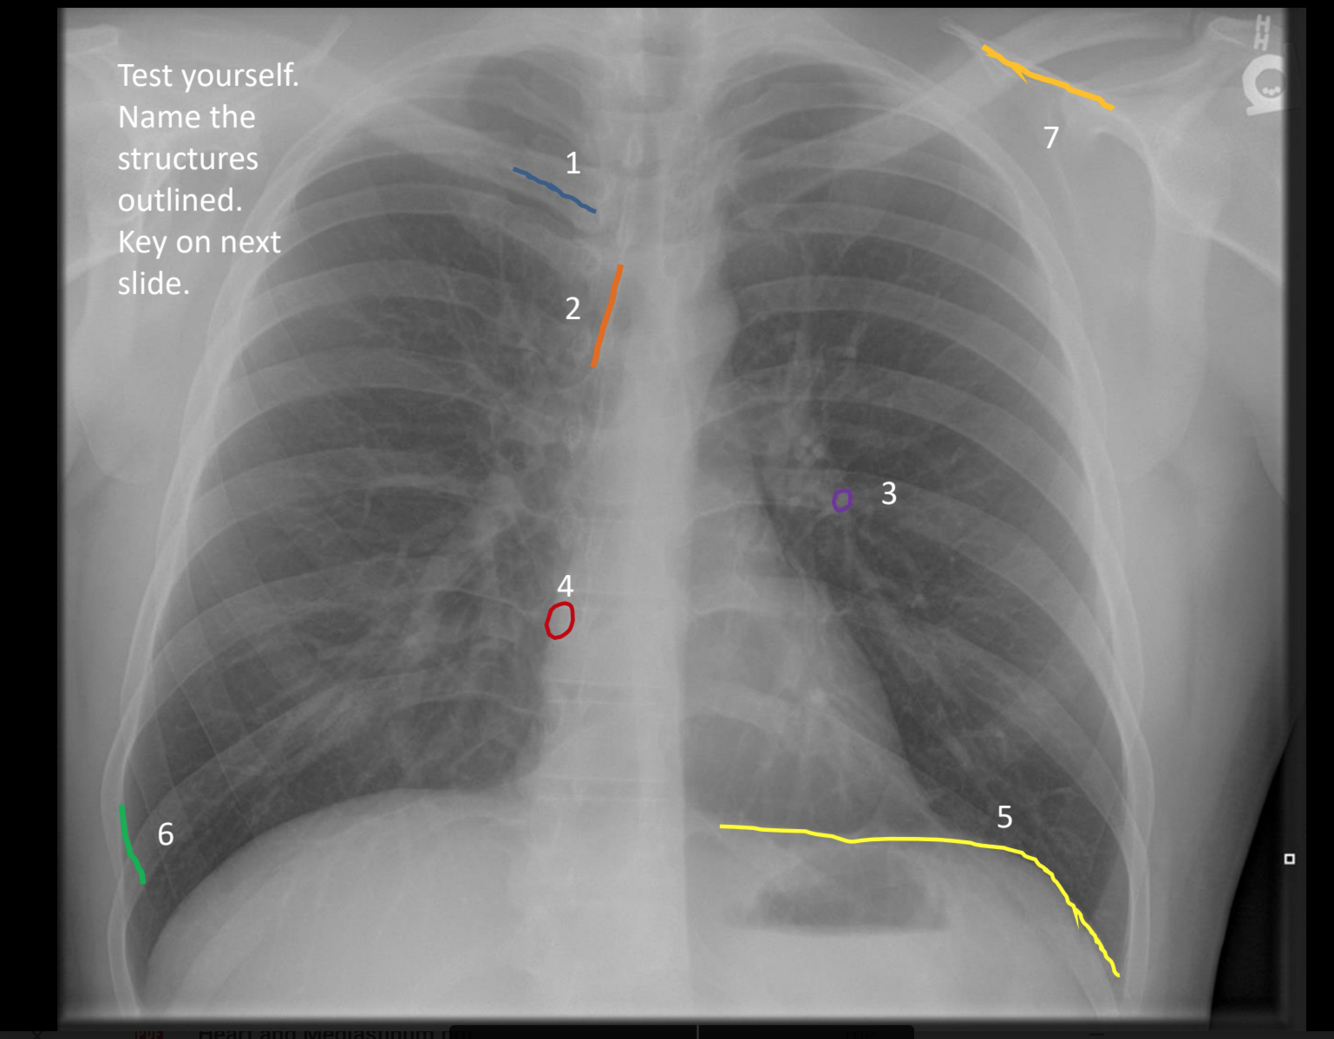

what is 7?

spine of left scapula

what is 6?

superior margin of anterior right rib 9

what is 5?

left hemidiaphragm